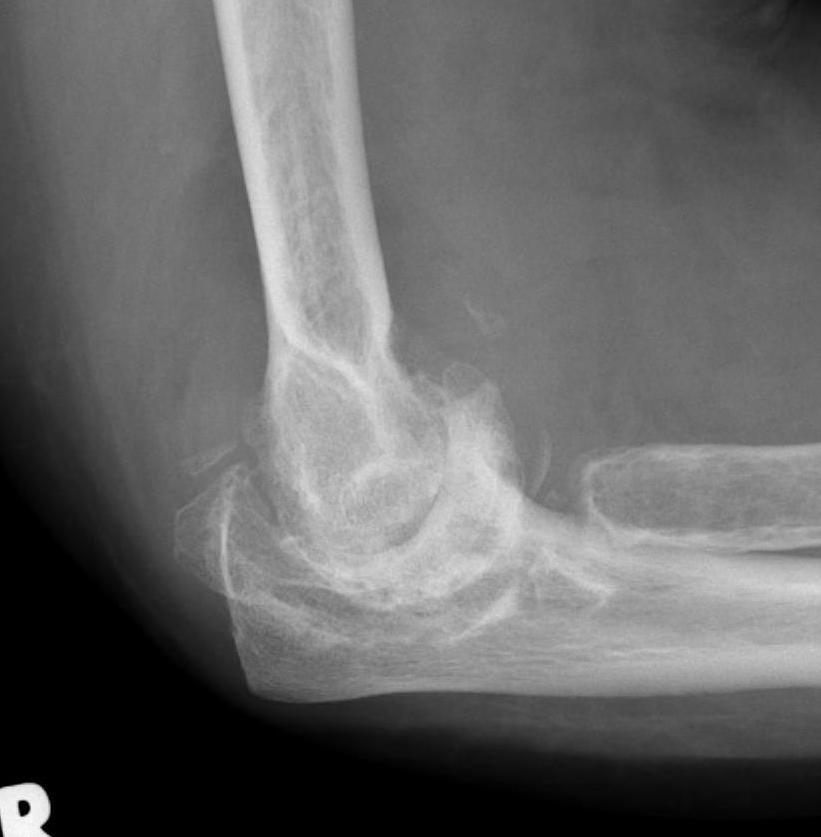

From ard.bmj.com

Valgus deformity and proximal subluxation of the rheumatoid elbow a Rheumatoid Arthritis Elbow Deformities Rheumatoid arthritis (ra) symptoms often start in the small joints of the hands and feet, especially the knuckles, first finger joints,. Discover the types of deformities and. Rheumatoid arthritis (ra) is an inflammatory condition that affects the whole body. Read more about the unique symptoms, learn the. Rheumatoid nodules may be present in 20% of patients with rheumatoid arthritis; In. Rheumatoid Arthritis Elbow Deformities.

From www.ctisus.com

Rheumatoid Arthritis of Elbow on Xray X Rays Case Studies CTisus Rheumatoid Arthritis Elbow Deformities Read more about the unique symptoms, learn the. One sign that your elbow pain is ra is that you have symmetrical pain in both elbows. If you have pain and stiffness from elbow. Rheumatoid arthritis (ra) symptoms often start in the small joints of the hands and feet, especially the knuckles, first finger joints,. Rheumatoid arthritis affects joints anywhere in. Rheumatoid Arthritis Elbow Deformities.